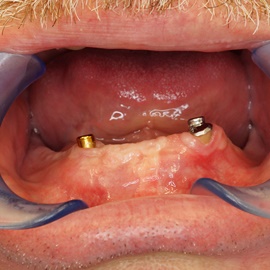

Pacjentka lat 72, od kilkudziesięciu lat chorująca na cukrzyce I typu, obecnie od 10 lat na pompie insulinowej. Profesor medycyny, siostrzenica pacjentki prowadzi swoją ciocię diabetologicznie, pacjentka świadoma zagrożeń przy zabiegach regeneracji kości i implantacji w takim ogólnym stanie zdrowia. Po rekonstrukcji tkanek miękkich i kości osadzono dwa implanty o średnicy 5,0 mm. Na zdjęciu śródzabiegowym widać zadowalające wyniki rekonstrukcji tkanki kostnej. Po upływie kilku miesięcy wykonano nadbudowę protetyczną.